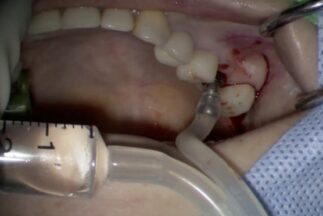

| 治療内容 | 上顎洞底挙上術(トランスクレスタル、水圧)による単独臼歯修復 |